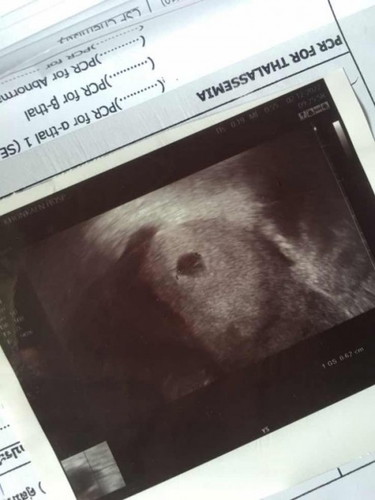

5week2day 👼🏻

ไปฝากครรภ์มาวันนี้ ซาวด์ผ่านช่องคลอดไม่เจอตัวน้องเจอแต่ถุงตั้งครรภ์ อีก 2 อาทิตย์คุณหมอนัดไปตรวจใหม่ ได้แต่ภาวนาให้เจอตัวน้อง แม่ๆซาวด์เจอน้องกันตอนกี่วิคค่ะ ?